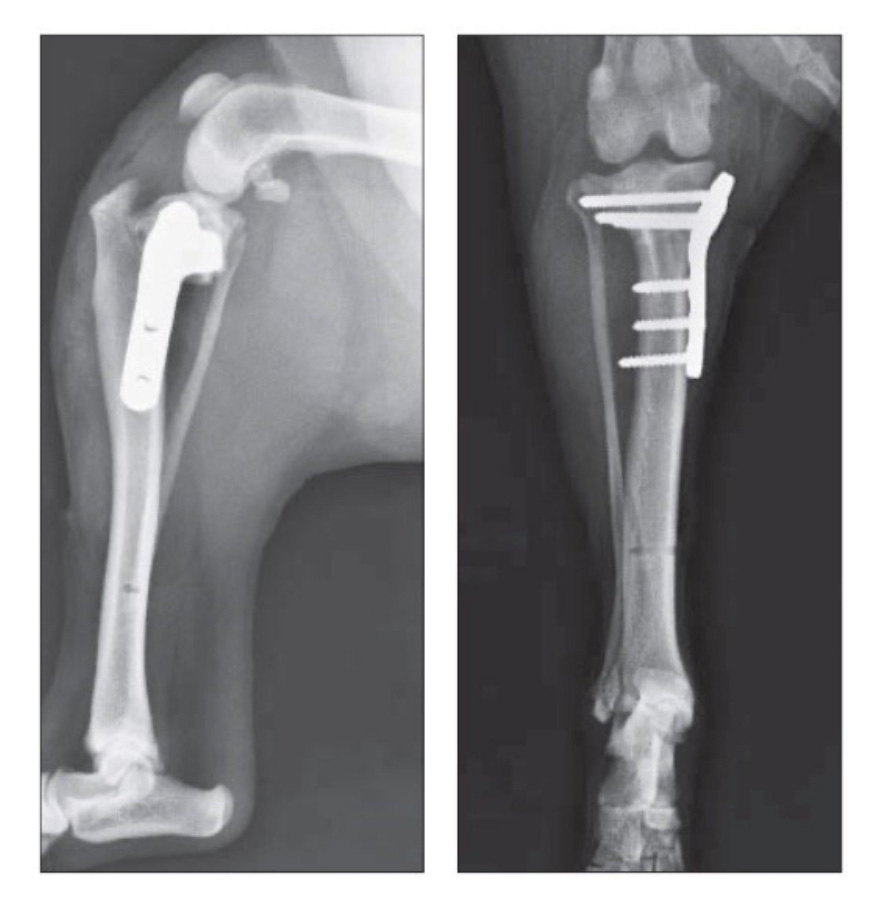

骨折

小型犬に頻発する骨折の一つである「橈尺骨(とうしゃくこつ)骨折」(前肢の骨折)は、的確な手術を行い強固な安定化をはからないと、骨が癒合しないケースも多く、特に注意しなければならない骨折の一つです。

骨折の整復には、熟練した手術チームによる精度の高いインプラント(スクリューやプレート等)技術が必要となります。

当院では、年齢や骨折部位、骨折の種類に応じ、最適な方法で治療を行います。